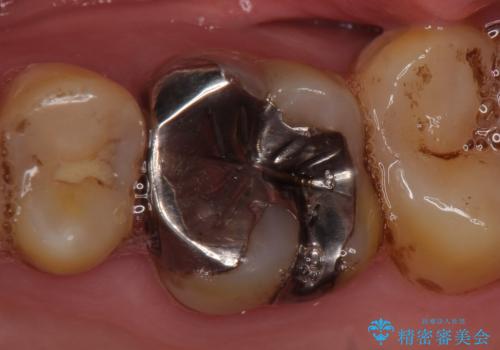

- 他院にて左上6番目の歯の神経が死んでいるといわれたので診て欲しいといらっしゃった方の症例です。

診査の結果左上6は失活していたため、根管治療を行った後にオールセラミッククラウンによる補綴を行いました。